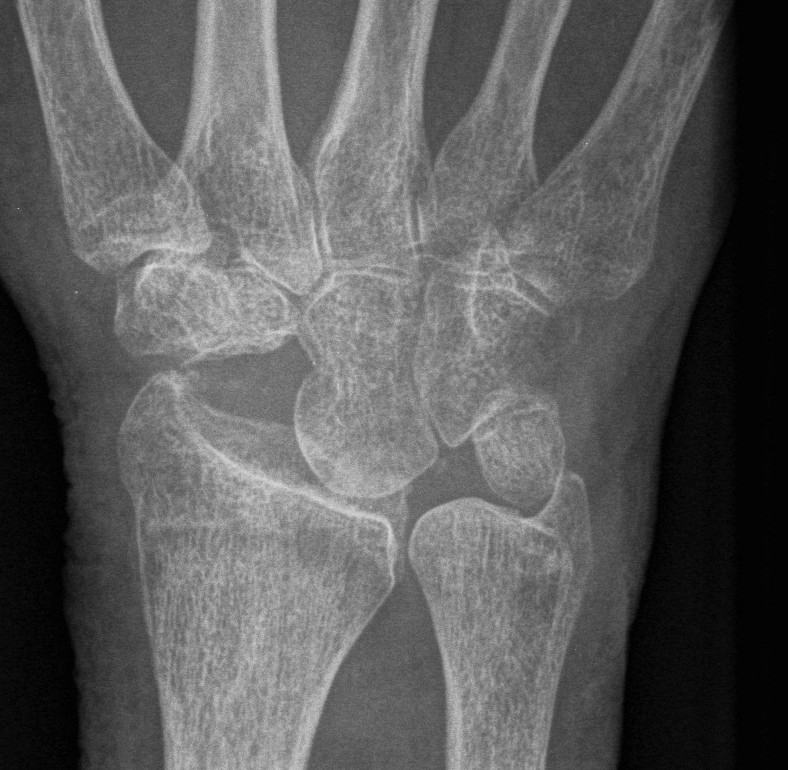

Definition

Scaphoid non union advanced collapse

Diagnosis

Xray / CT

- non union of scaphoid

- radio-scaphoid OA